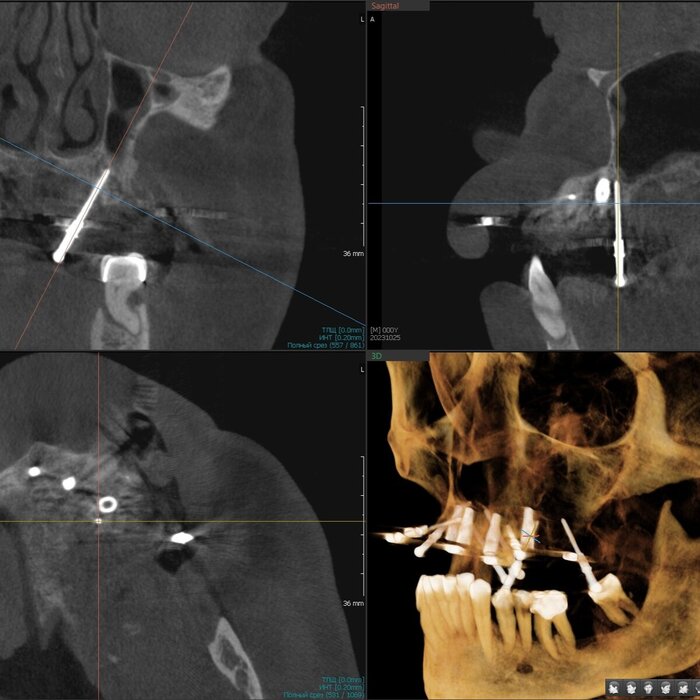

Я делаю транскрестальный синус-лифтинг в 95% случаев последние пару лет, даже если толщина кости меньше 1 миллиметра, но, за счет опыта понимания свойств слизистой гайморовой пазухи наощупь и использования определенных материалов непосредственно в процессе, могу поднять её, зачастую, более чем на 10 мм через дырку диаметром всего 4-5 мм без разреза десны на половину челюсти. Причем, как правило, без использования молотка. Как-то так.

Соответственно разрез меньше, рожа потом практически не распухает, процедура проходит комфортнее, несмотря на её техническую сложность. К тому же мы забываем про риск кровотечения из задней верхней альвеолярной артерии, которая проходит как раз в толще стенки пазухи и часто повреждается при классическом открытом синус-лифтинге. В плане затрат на материал тоже выгоднее, можно сэкономить как собственные деньги, так и деньги пациента. Однако, в голове надо держать то, что данный вид синус-лифтинга требует высоких мануальных навыков врача, ювелирной точности, а также смелости, так как тут шаг влево, шаг вправо-расстрел. Также в любой момент в случае чего нужно быть готовым перевести свой синус-лифтинг в открытый.